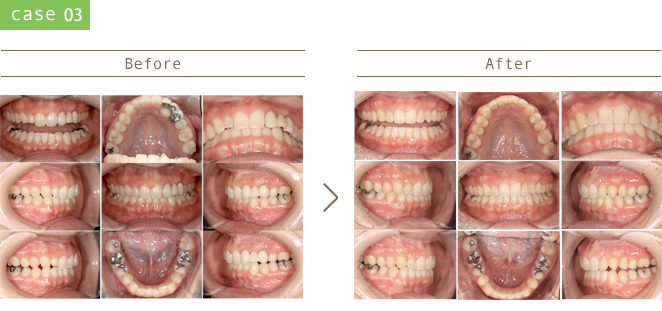

治療後20年・30年後を考え、患者さんが一生噛めることを目指した治療計画を心がけています。

審美的、骨格的、機能的、生態的な観点を包括的に鑑みて治療を行っています。

虫歯の再発リスクの少ない治療、歯周病の発症・進行を防ぐためのメンテナンスに注力しています。